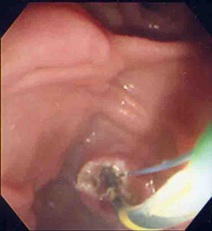

乳頭を太いバルーンで拡張(写真左)、大きな結石を取り出した(写真右)。